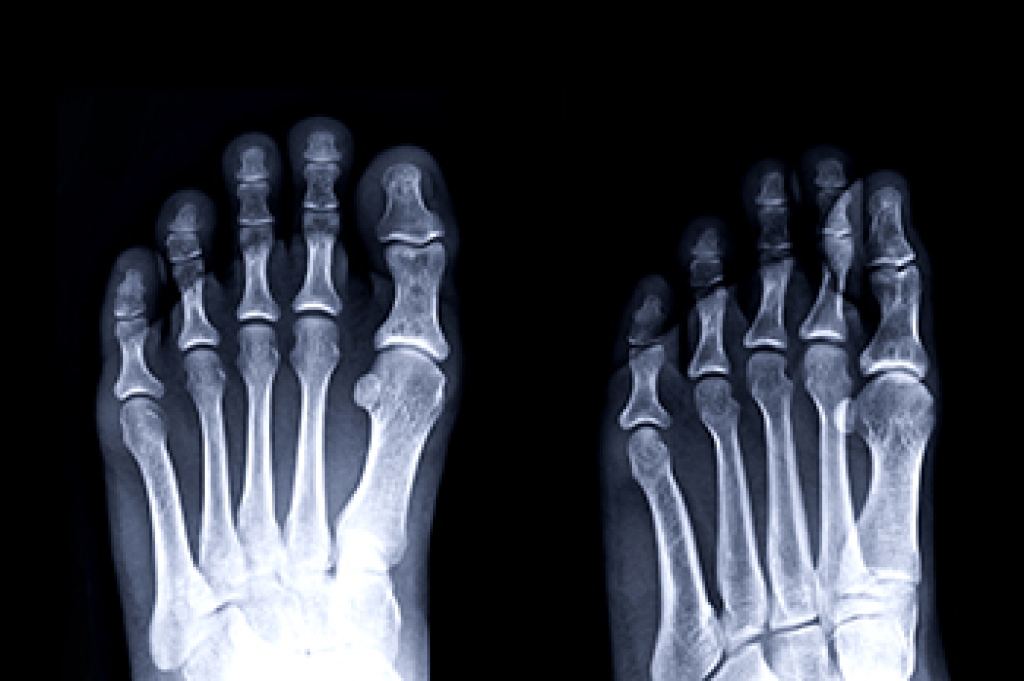

Foot problems related to diabetes can escalate quickly if not promptly addressed. Signs of serious issues include persistent numbness or tingling in the feet that could indicate nerve damage, known as neuropathy. Skin changes such as dryness, cracking, or peeling, particularly when accompanied by slow-healing sores or wounds, are concerning, as diabetes impairs circulation and wound healing. Swelling or redness surrounding a foot ulcer may indicate infection, a serious complication requiring immediate medical attention. Changes in foot shape, such as hammertoes or bunions, can also occur due to nerve damage and altered mechanics. Any sudden change in foot temperature or color warrants evaluation, as these can signal compromised blood flow. Regular foot exams by a podiatrist and diligent foot care routines are vital for managing diabetes and preventing serious foot complications. If you have foot problems related to diabetes, it is strongly suggested that you are under the care of this a podiatrist who can help you to manage this condition.

Diabetes affects millions of people every year. The condition can damage blood vessels in many parts of the body, especially the feet. Because of this, taking care of your feet is essential if you have diabetes, and having a podiatrist help monitor your foot health is highly recommended.